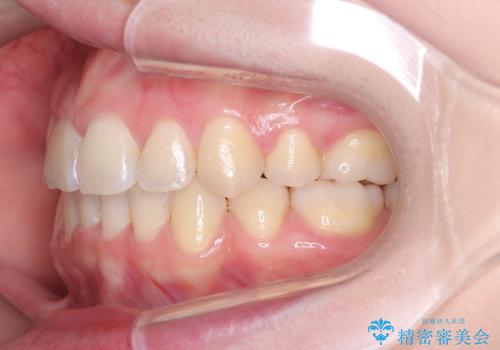

- 患者様は、結婚式までに歯並びを整えたいとのご要望で来院されました。診断の結果、上下左右の第一小臼歯を抜歯し、歯列全体を整える計画としました。審美性を重視し、目立ちにくいホワイトワイヤーを使用した矯正を提案しました。治療期間は2年を目安とし、結婚式までに前歯の整列と噛み合わせを優先的に整えるスケジュールで進めました。定期的な調整と経過観察を通じて、計画的に治療を進めました。

結婚式までに仕上げるため、通常よりも細かく調整を行い、歯の動きを効率的に管理しました。審美ワイヤーを使用したことで、治療中も目立ちにくく、写真撮影などの日常生活での見た目の負担を軽減しました。抜歯部分のスペースを閉じる際には、前歯の位置や噛み合わせのバランスに配慮し、過度な力がかからないよう進めました。患者様の大切なイベントに間に合うよう治療計画を立て、理想的な仕上がりを実現しました。